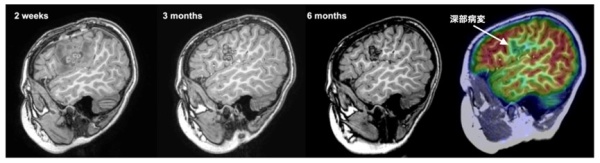

本研究では薬物療法のみでは発作が制御できなかった小児の島弁蓋部てんかん患者2名を対象にVolume-based RFTCを行い、合併症を残すことなく発作消失を得ることに成功しました。治療後急性期には凝固した病変の周囲に浮腫が生じますが、最終的にこの浮腫は6か月後には消失し、浮腫に伴う永続的な合併症は生じませんでした。また治療から6か月後のMRIでは、深い場所の病変のみが正確に治療されていることがわかりました(図3)。

図3:治療半年後のMRIを見ると深部の病変のみが 正確に治療されていることが明らかになった